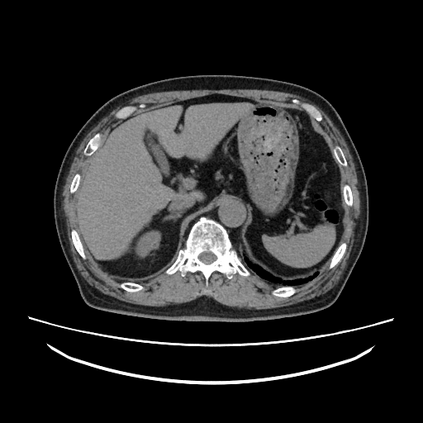

We propose a novel continual self-supervised learning (CSSL) framework for simultaneously learning diverse features from multi-window-obtained chest computed tomography (CT) images and ensuring data privacy. Achieving a robust and highly generalizable model in medical image diagnosis is challenging, mainly because of issues, such as the scarcity of large-scale, accurately annotated datasets and domain shifts inherent to dynamic healthcare environments. Specifically, in chest CT, these domain shifts often arise from differences in window settings, which are optimized for distinct clinical purposes. Previous CSSL frameworks often mitigated domain shift by reusing past data, a typically impractical approach owing to privacy constraints. Our approach addresses these challenges by effectively capturing the relationship between previously learned knowledge and new information across different training stages through continual pretraining on unlabeled images. Specifically, by incorporating a latent replay-based mechanism into CSSL, our method mitigates catastrophic forgetting due to domain shifts during continual pretraining while ensuring data privacy. Additionally, we introduce a feature distillation technique that integrates Wasserstein distance-based knowledge distillation (WKD) and batch-knowledge ensemble (BKE), enhancing the ability of the model to learn meaningful, domain-shift-robust representations. Finally, we validate our approach using chest CT images obtained across two different window settings, demonstrating superior performance compared with other approaches.